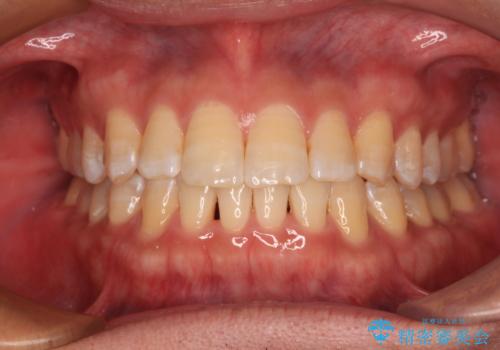

[ マウスピース矯正 ] 出っ歯に見える前歯を改善したい

![[ マウスピース矯正 ] 出っ歯に見える前歯を改善したいの症例 治療前](https://seimitsushinbi.jp/wp/wp-content/uploads/2023/10/IMG_6858-500x350.jpg?v=1697014973)

![[ マウスピース矯正 ] 出っ歯に見える前歯を改善したいの症例 治療後](https://seimitsushinbi.jp/wp/wp-content/uploads/2023/10/8a6c9bf89570c0c75da0a5fabd1cd70e-500x350.jpg?v=1697014858)